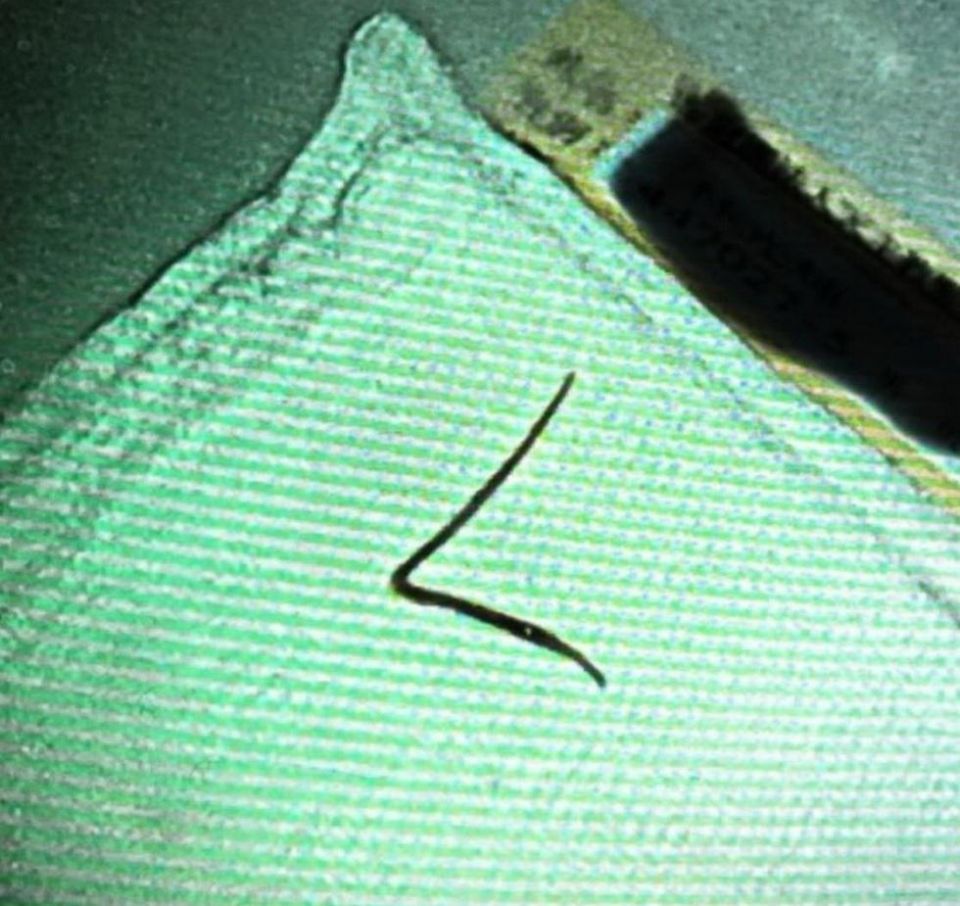

在家人建議下至天主教聖馬爾定醫院求診,肝膽腸胃科醫師羅清池建議他做大腸鏡,檢查中發現原來有一根長約四公分的魚刺,就卡在乙狀結腸,兩端就牢牢地刺在大腸壁上,醫師馬上使用專用的金屬夾,成功將魚刺夾出。取出魚刺後的隔天,腹部疼痛明顯改善,讓阿伯非常高興。

羅清池醫師表示,通常魚刺會卡在消化道的三個狹窄處,由上而下分別為賁門、幽門、及廻盲瓣,以阿伯這麼長的魚刺,居然可以「身騎白馬走三關」,一路漂流到乙狀結腸才卡住,實在少見。而且魚刺兩端就卡在腸壁上,差點就會造成腸穿孔,真的非常危險,所幸成功將它夾出,不然也有可能會造成腹膜炎或敗血症。